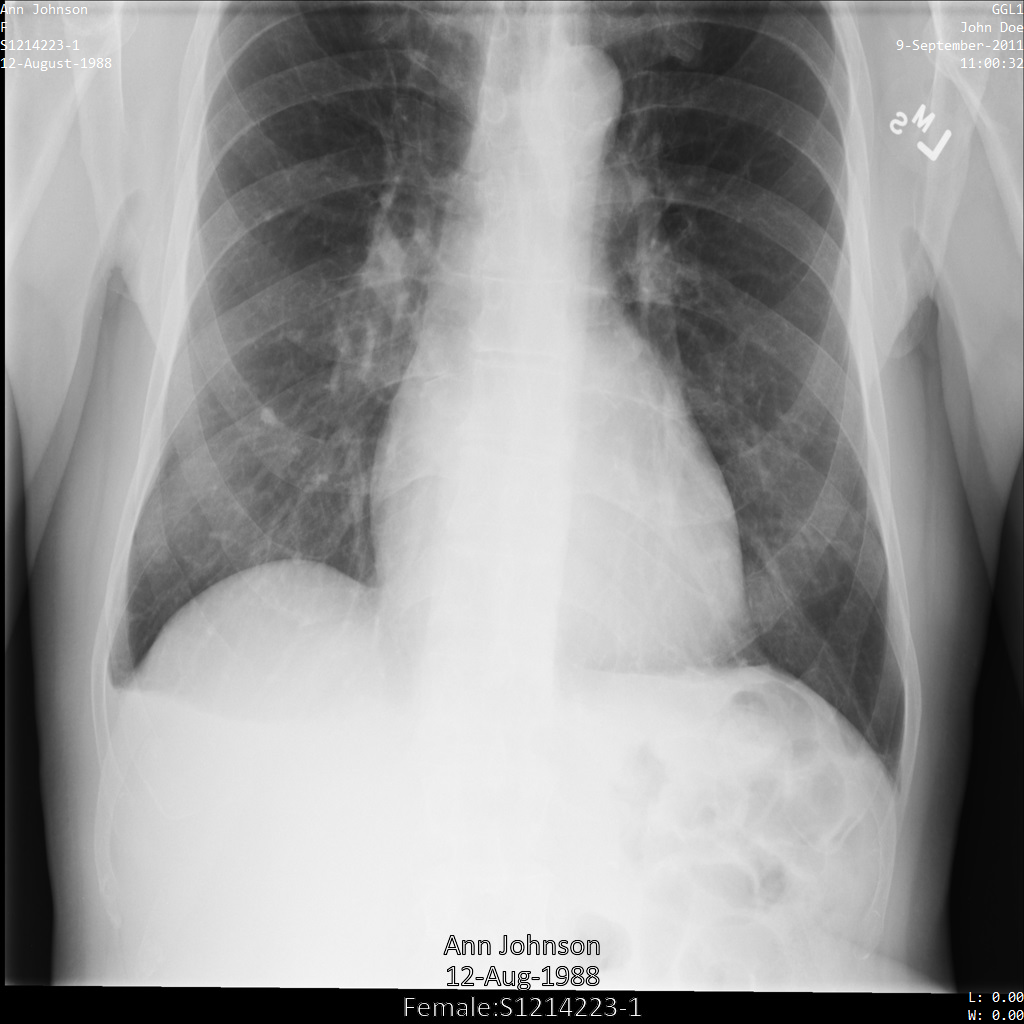

以下の各セクションでは、DICOM データを匿名化するさまざまな方法について、例を示しています。また、それぞれの例で匿名化された出力画像を示しています。各例では、入力として以下の元画像を使用しています。

各匿名化オペレーションからの出力イメージをこの元のイメージと比較して、オペレーションの効果を確認できます。

Cloud Healthcare API に画像を送信すると、画像は次のように表示されます。画像の上部隅に表示されているメタデータは削除されていますが、画像の下部にある焼き付き保護対象保健情報(PHI)は残ります。焼き付きテキストも削除するには、画像の焼き付きテキストを削除するをご覧ください。